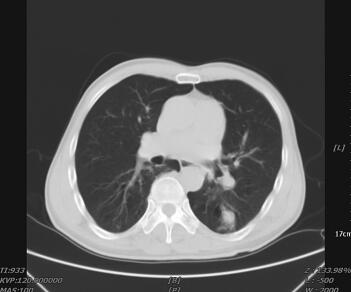

辅助检查:血常规:WBC 14.03×109/L,N 70.74%,L 21.84%,Hb 122g/L。尿葡萄糖阴性;尿酮体(+)。血气分析:pH 6.765;氧分压167mmHg;二氧化碳分压12.4mmHg;实际剩余碱−32.7mmol/L;实际碳酸氢根1.7mmol/L;阴离子隙25.9mmol/L。血浆乳酸> 12mmol/L(鼻氧管吸氧,氧浓度3L/min)。血葡萄糖5.4mmol/L;血尿素氮9.7mmol/L。凝血酶原时间15.30秒;活化部分凝血活酶时间78.20秒;凝血酶时间86.9秒;D-二聚体0.51mg/L。B型脑钠肽339pg/ml;心肌酶谱:心肌肌酸激酶153U/L;α-羟丁酸脱氢酶252U/L;谷草转氨酶136U/L;肌酸磷酸激酶2235U/L;乳酸脱氢酶339U/L。心电图检查:窦性心律不齐,左心室肥厚,部分导联ST段改变,QT间期轻度延长。腹部立位片未见异常。胸部CT见肺内多发斑片状高密度影,边缘粗糙(图1)。

图1 入院时胸部CT可见肺内多发斑片状高密度影,边缘粗糙

另外,在诊断中还要注意糖尿病患者急性并发症乳酸性酸中毒和酮症酸中毒的鉴别。其中糖尿病酮症酸中毒(DKA)是血糖急剧升高引起的胰岛素的严重不足激发的酸中毒,主要特点是胰岛素严重缺乏和脱水;乳酸性酸中毒系不同原因引起的血乳酸持续增高和pH减低(<7.35)的异常生化改变所致的临床综合征,后果严重,死亡率高。乳酸性酸中毒临床上分为A、B两型。A型为继发性乳酸性酸中毒,较B型常见得多,其发病机制是组织获得的氧不能满足组织代谢需要,导致无氧酵解增加,产生A型乳酸性酸中毒,包括各种休克、右心衰竭、心排血量减少、窒息、低氧血症、CO中毒、危及生命的贫血等。B型为自发性乳酸性酸中毒,其发病机制与组织缺氧无关。可进一步分为3种亚型,B1型与糖尿病、脓毒血症、肝肾衰竭等常见病有关,B2型与药物或毒物有关,B3型与肌肉剧烈活动、癫痫大发作等其他因素有关。该患者发生乳酸性酸中毒是因为:①血糖控制不佳。②糖尿病其他急性并发症:如感染、酮症酸中毒、糖尿病非酮症高渗综合征时可成为糖尿病乳酸性酸中毒的诱因。结合患者肺部CT检查结果,患者肺部感染是发生乳酸性酸中毒的一个重要诱因。③大量服用苯乙双胍:双胍类药物,尤其是苯乙双胍能增强无氧酵解,抑制肝脏及肌肉对乳酸的摄取,抑制糖异生作用,故有致乳酸性酸中毒的作用。结合该患者平时长期服用苯乙双胍控制血糖,有诱发乳酸性酸中毒的可能。

2.糖尿病患者的乳酸性酸中毒不如酮症酸中毒多见。这两者都是糖尿病患者需要紧急处理的严重情况,但两者在发病原因、病理生理机制和处理方法上大相径庭,因此临床医师面临一些疾病的并发症时,既要考虑常见的并发症,也要考虑少见的并发症,而这些区别正是通过一些不被大家注意的临床表现和实验室检查的结果反映出来,该病例的首诊医师正是注意到了这一点,根据患者血糖控制不佳,糖尿病其他急性并发症,如感染、酮症酸中毒、糖尿病非酮症高渗综合征可成为糖尿病乳酸性酸中毒的诱因。结合患者肺部CT检查结果,患者肺部感染是发生乳酸性酸中毒的一个重要诱因。同时患者大量服用苯乙双胍能增强无氧酵解,抑制肝脏及肌肉对乳酸的摄取,抑制糖异生,故有致乳酸性酸中毒的作用。实验室检查尿葡萄糖(+);尿酮体(+);血气分析:pH 6.765,氧分压167mmHg,二氧化碳分压12.4mmHg,实际剩余碱−32.7mmol/L,实际碳酸氢根1.7mmol/L,阴离子隙25.9mmol/L;血浆乳酸>12mmol/L(鼻氧管吸氧,氧浓度3L/min);血葡萄糖5.4mmol/L,根据上述情况和客观检查指标,及时诊断出该患者为糖尿病乳酸性酸中毒。